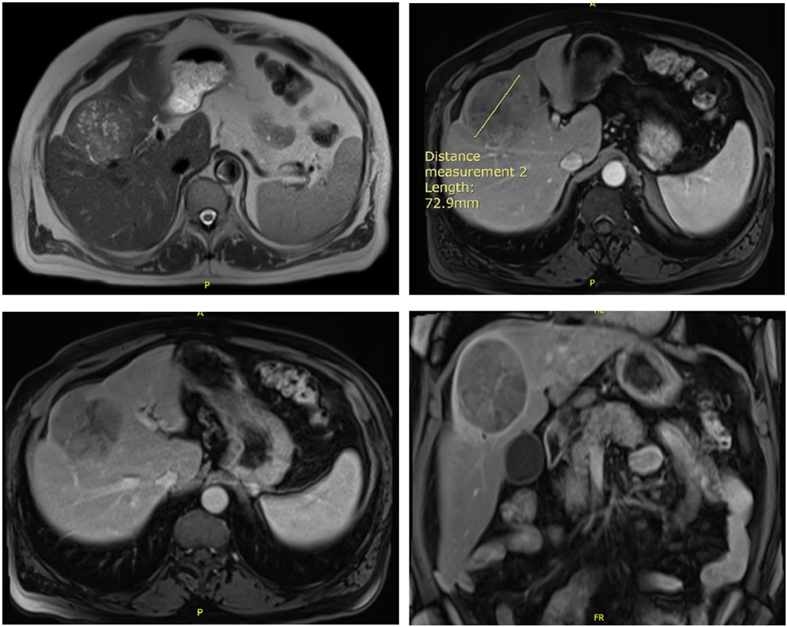

A CT scan abdomen pelvis was then ordered for better assessment of the liver mass and showed a 7.8×6 cm heterogeneous, hypodense mass in segment IV of the liver with low vascularity after contrast injection. A suspected mass that needs confirmation with a biopsy. Biopsy of the mass showed the presence of cells compatible with hepatocellular carcinoma confirmed by an immunostaining positive for Hep Par 1. CT scan of the chest was negative for distant metastasis. MRI of the abdomen showed 8×7.5×6.5 cm well marginated round encapsulated mass in the liver subcapsular parenchyma involving segments IVa/VIII superiorly and IVb inferiorly with heterogenous signal intensity on the T1 and T2 sequences corresponding areas of fibrosis, fatty changes and necrosis. After gadolinium administration, arterial diffuse enhancement of the mass with washout and delayed capsular enhancement on the late phases was seen. No evidence of cirrhotic changes (Figure 1).

Figure 1: MRI of the abdomen showing an 8×7.5×6.5 cm well marginated round encapsulated mass in the liver subcapsular parenchyma involving segments IVa/VIII superiorly and IVb inferiorly with heterogenous signal intensity on the T1 and T2 sequences.